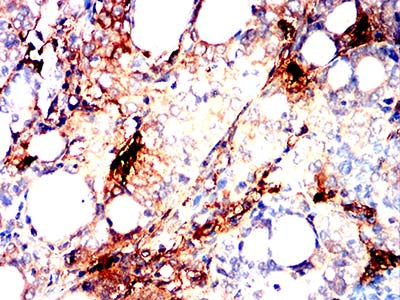

Immunohistochemical analysis of paraffin-embedded human lung cancer tissues using TPSAB1 mouse mAb with DAB staining.